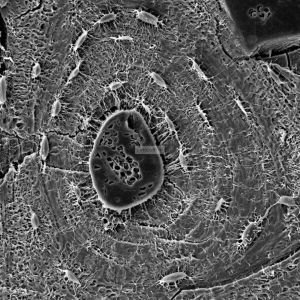

透射电镜